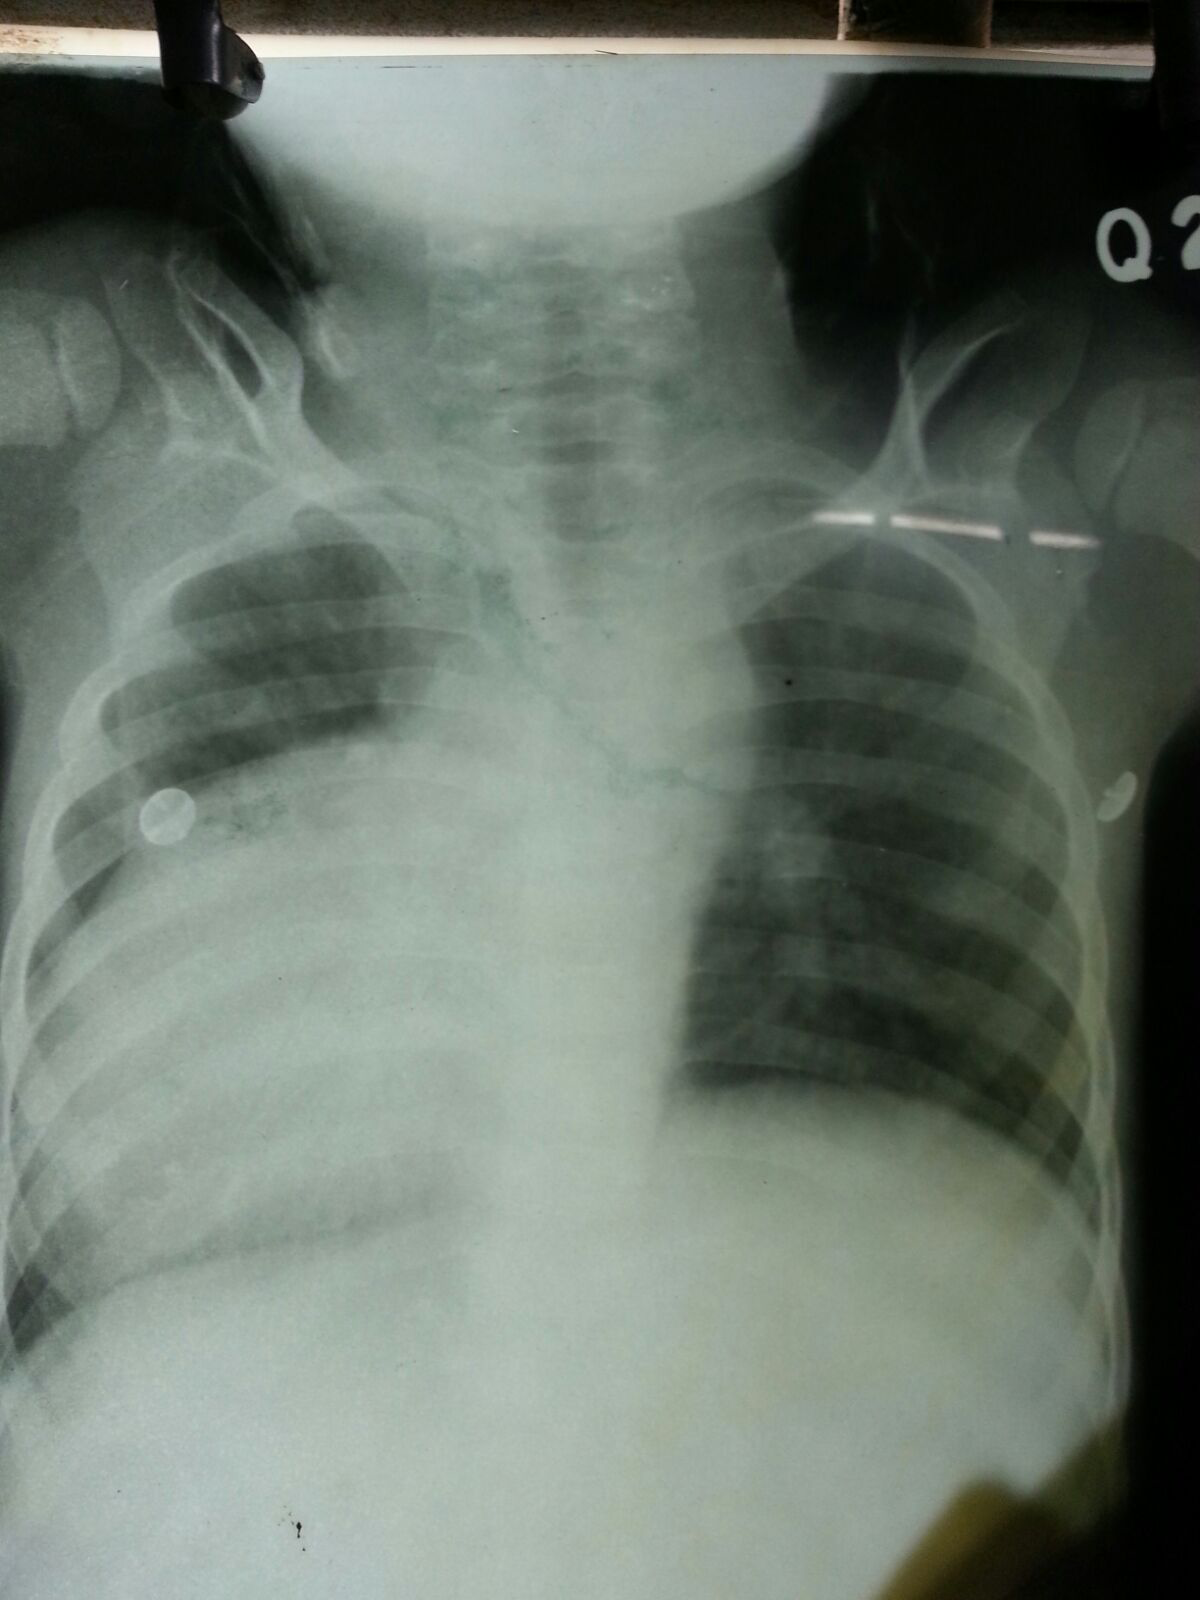

A nine year old, male child presented in the emergency with 2-3 episodes of seizure, high grade fever and respiratory distress since 15 days. Seizure were of generalized tonic clonic type and was associated with drooling of saliva, uprolling of eyeball, spontaneous micturition of urine and cyanosed limb and face. Immediately intravenous lorazepam 2mg were given in bolus dose and intubated with PVC cuffed endotracheal tube 6 mm ID and controlled mode of ventilation were started. This was accomplished by rapid sequence intubation technique using inj thiopentone 5mg/kg and inj rocuronium 1mg/kg. Then patient was shifted to intensive care unit, where bedside 2D-echocardiography and chest roentogram were done. The 2-D echocardiography revealed atrioventricular and ventriculo atrial concordance, D-TGA, large patent foramen ovale, right to left shunt, moderate pulmonary artery hypertension and the chest roentogram revealed egg on side appearance with presence of infiltrates in the Right Lower Lobe. Routine investigations, blood culture, tracheal tube culture and serum procalcitonin levels were sent. Antibiotic coverage were started in view of suspected aspiration during seizure and a non-contrast CT scan of brain were ordered following seizure episode which revealed ring enhancing lesion in left temporal lobe causing mild mass effect and moderate surrounding edema with abnormal leptomeningeal enhancement (S/O: Abscess? Tubercular?). Laboratory investigations showed Hb-22.4g% with Hct-64.9%, platelets counts- 142,000/mm3, and Total leucocyte count-14,600/mm3 with normal liver and renal function tests

Incidence of preoperative morbidity and mortality.7,8 Suggested modalities for the treatment of this occurrence are hyperventilation with an inspired oxygen concentration (FiO2) of 1.0, judicious administration of volume, use of vasoconstrictors to elevate SVR, and control of wide variations of the heart rate.6–8 Hence judicious preoperative hydration is very necessary. Till date there is no conclusive anaesthetic plan for TGA with brain abscess. Preoperatively, an understanding of the patient’s underlying pathophysiology, coupled with knowledge of the effects of anesthesia on the anomalous myocardium, is crucial. Although extensive preoperative evaluations by the patient’s intensivist, cardiologist, and cardiac surgeon are preferable, they may not be readily available, as were the case with this patient. Careful review of the patient’s preoperative medication profile, with attention to potential anesthetic interactions, must be considered (Figure 1 & 2).

Figure 1